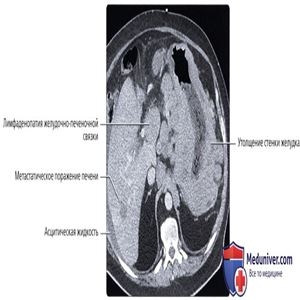

КТ с контрастированием, аксиальный срез: определяется распространенное опоясывающее утолщение стенки желудка по всей площади и увеличение множества региональных лимфоузлов (в особенности в желудочно-печеночной связке). Также обратите внимание на небольшой очаг низкой плотности в правой доле печени. При обнаружении такой выраженности лимфаденопатии следует предполагать лимфому, и в этом случае окончательным диагнозом стала неходжкинская лимфома.